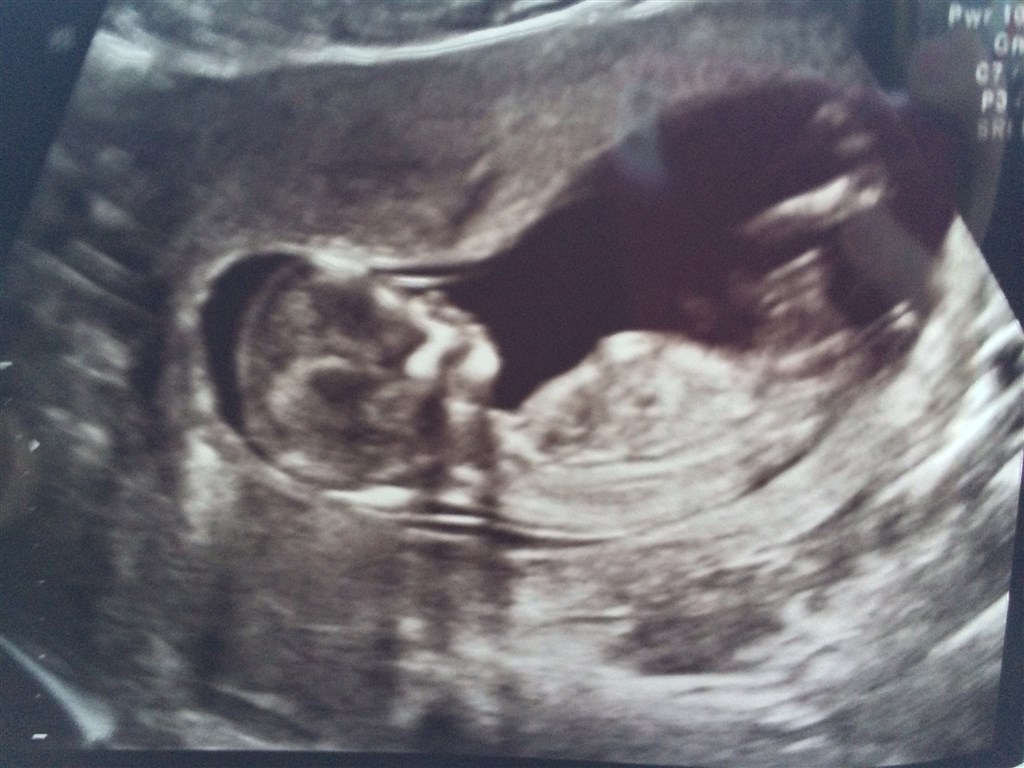

Vi har idag været til NF scanning og set en helt perfekt lille sprællebasse! Den lå og vinkede og fik også lige en tår fostervand.

Det var så vildt at opleve, og nu bliver det hele pludselig mere virkeligt! Det er jo en lille miniature baby jeg har i maven!!

Vi fik en meget lav risikovurdering på 1:<20.000 og alt så normalt og fint ud.

Blev desuden rykket 3 dage frem, så termin hedder nu 4/6.